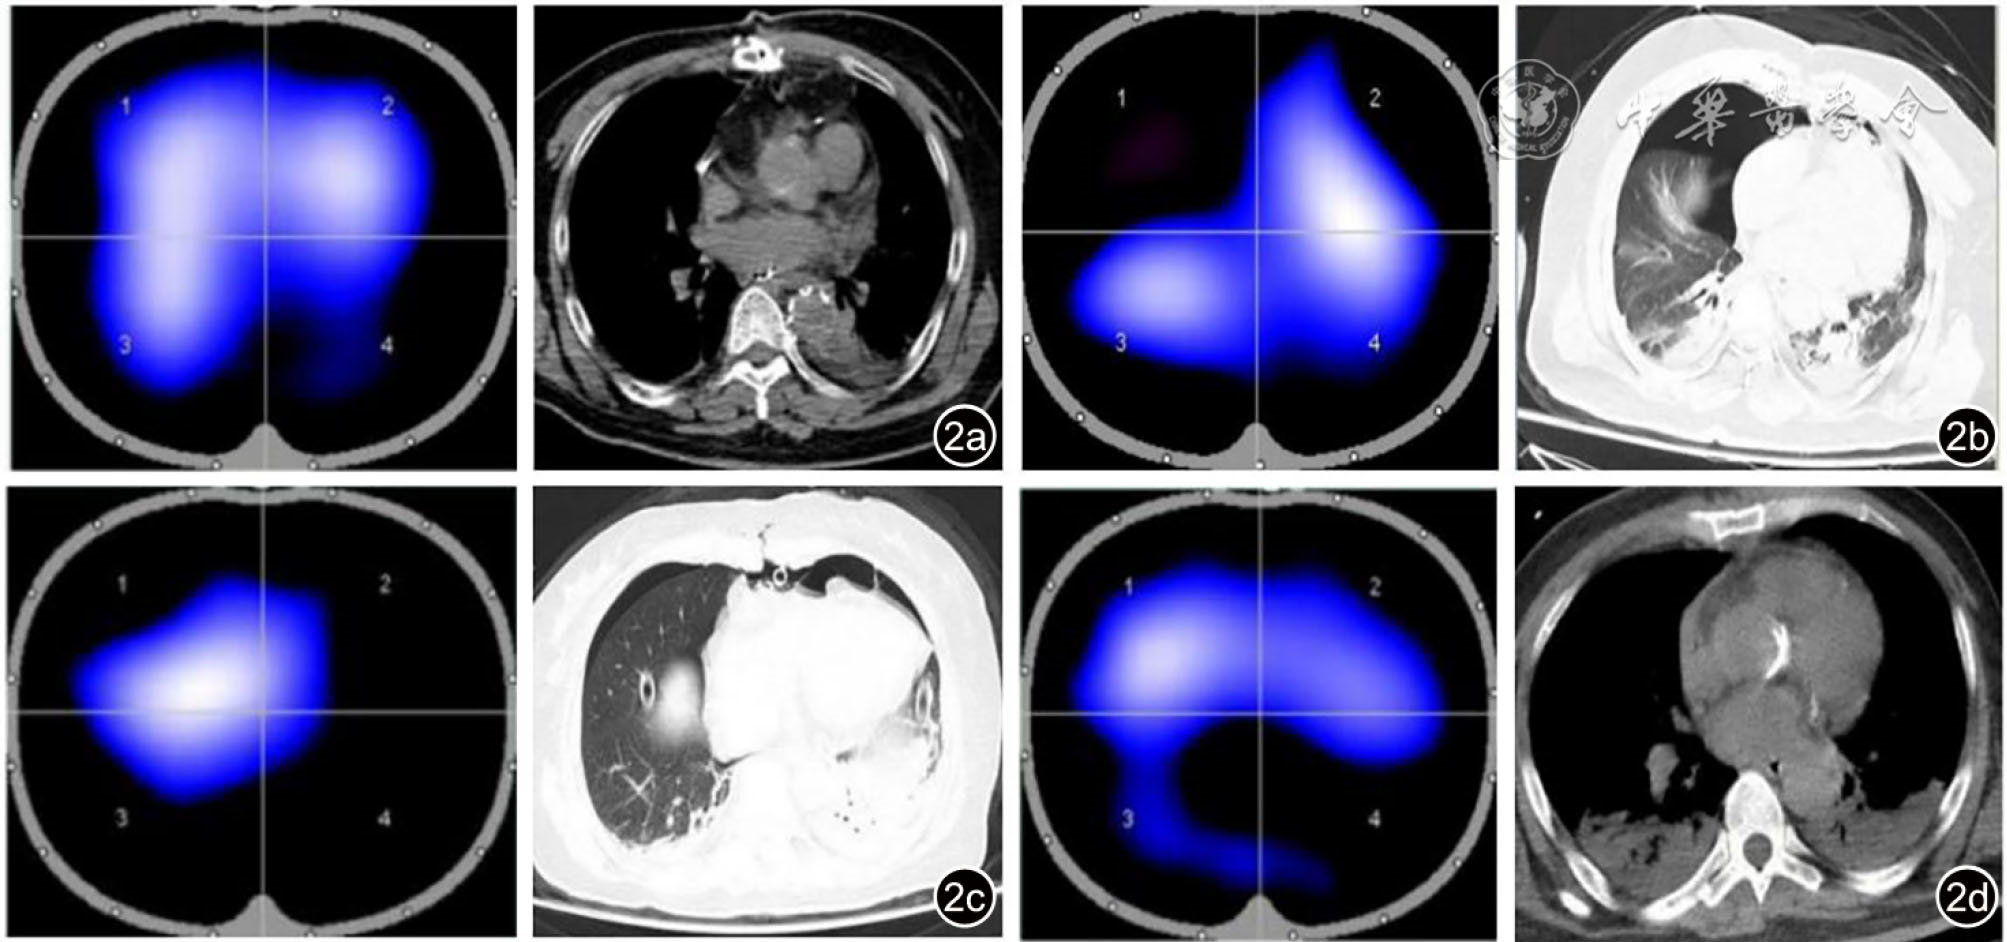

Postoperative pulmonary complications (PPC) are one of the most challenging complications faced by patients after cardiac surgery, and are the major cause of postoperative mortality. Electrical impedance tomography (EIT) is a kind of noninvasive bedside lung ventilation monitoring technology which is used increasingly in intensive respiratory management. Recently, it has been found that EIT lung ventilation imaging features can be used to predict the occurrence of PPC after abdominal surgery. Based on the practical experience of EIT application in our center, this paper summarizes the PPC diagnosis and treatment strategy based on EIT lung ventilation image feature, in order to provide reference for the application of EIT technology in cardiac surgery.